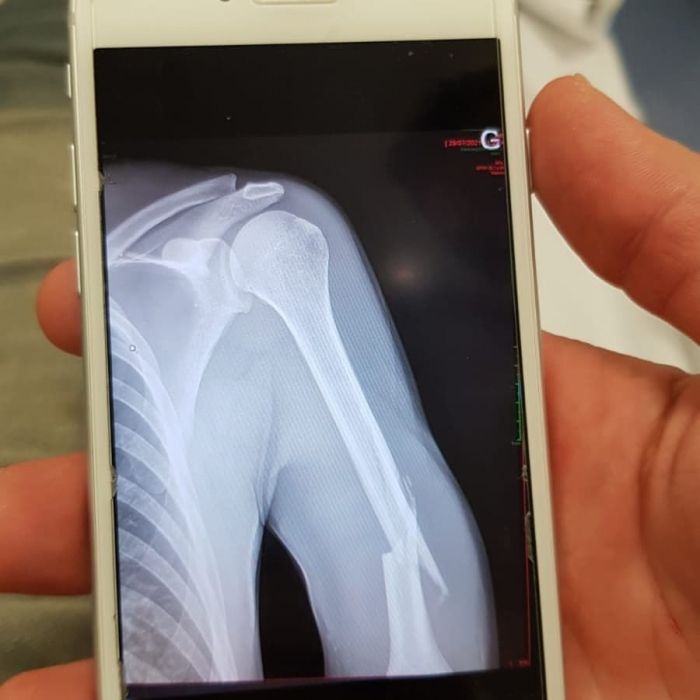

Luc est au repos forcé pendant encore 2 bons mois suite à sa fracture de l'humérus.

Il garde le moral malgré des douleurs encore intenses.